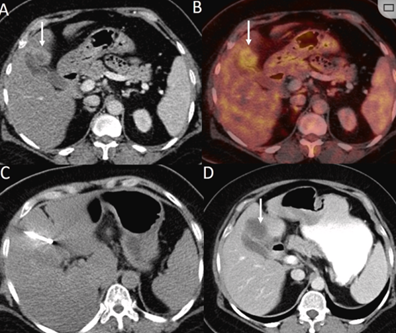

CT引導(dǎo)的冷凍消融

(b) 冷凍消融術(shù)中影像顯示冰球完全覆蓋病變。(c) 19個月后隨訪,沒有發(fā)生局部腫瘤進展。完全消融率為97%(66/68);2名患者均接受了額外的冷凍消融,隨后實現(xiàn)完全消融。平均隨訪期為 12.8 個月(范圍:3-27 個月)。所有患者均接受影像復(fù)查(CT 或 MRI)。11個病灶(16.2%)檢測到局部腫瘤進展,6、12和18個月時的累積局部腫瘤進展率分別為4%、8.2%和20.5%。8例出現(xiàn)遠(yuǎn)處肝內(nèi)或肝外病變的患者接受經(jīng)動脈化療栓塞、經(jīng)動脈化療栓塞加射頻消融治療或全身化療。

主要和次要并發(fā)癥發(fā)生率分別為3.5%(2/57)和22.8%(13/57)。并發(fā)癥主要表現(xiàn)為局部皮膚凍傷、中度氣胸、發(fā)熱,僅有少數(shù)患者接受治療,多數(shù)患者自行恢復(fù)。所有患者能耐受圍手術(shù)期疼痛,VAS 評分范圍在 1-3 分之間(平均 1.65分)。3例患者術(shù)后疼痛加重,VAS評分達(dá)到4~5分,患者口服止痛藥后逐漸緩解。所有患者術(shù)后1天血常規(guī)、白細(xì)胞計數(shù)均升高,血小板均有不同程度下降,但變化值均在正常范圍內(nèi)。肝功能1個月后逐漸恢復(fù)到正常水平。